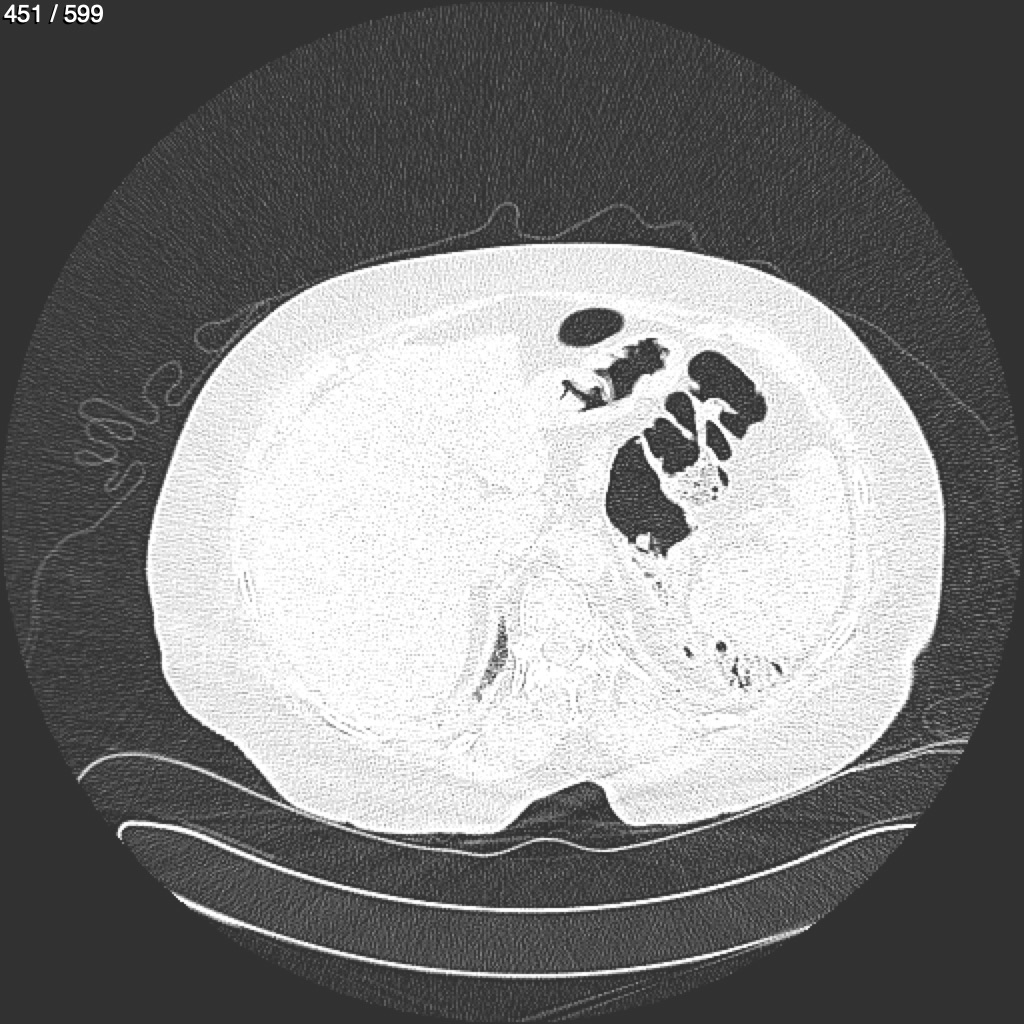

Home G​l​o​r​i​a​ ​G​l​a​d​y​s​ ​B​e​a​s​l​e​y​ ​-​ ​T​ó​r​a​x​ ​T​o​r​a​x​_​S​i​m​p​l​e​ ​(​A​d​u​l​t​o​)